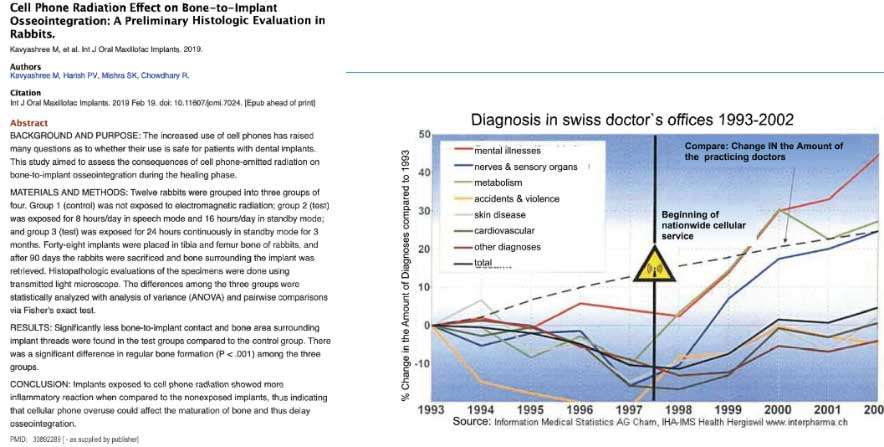

One out of two Americans suffer from immune disorders. If we look attentively at the changes occurring in our environment, we will notice some trends running in parallel: an exponential increase in chronic diseases, a similarly exponential trend of increasing strain on our immune system, but also an exponential increase in organic nutritional and behavioral concepts (Figure 1 and Figure 2).

Chronic diseases, such as cancer, ALS, Alzheimer’s disease, Parkinson’s disease, MS, Crohn’s disease and chronic fatigue syndrome, Breast Cancer are increasing at an explosive rate, and extrapolation of the curves shows that within a few years, everyone living in the Western world will be affected by at least one of these diseases.

A change in mindset is urgently required, as there are unfortunately certain factors in our environment that pose a progressively intensive risk to our health: increasing electromagnetic radiation in the form of high gigahertz frequencies related to mobile communications, WLAN and DECT technology. Also, the addition of titanium oxide (E171) to cosmetics, sun screen, oral contraceptives, toothpaste, chewing gum and even yogurt has led to an increasing intolerance to titanium, which is still being used in alternative medicine and traumatology. Yet even in its purest form ‘Grade 1 titanium’, this chemical element still contains up to 0.20 % iron and traces of nickel as well. This is an alarming fact when you consider that 80% of women in Europe experience an allergic reaction to nickel. More significant risk factors present the intraoral interference fields.